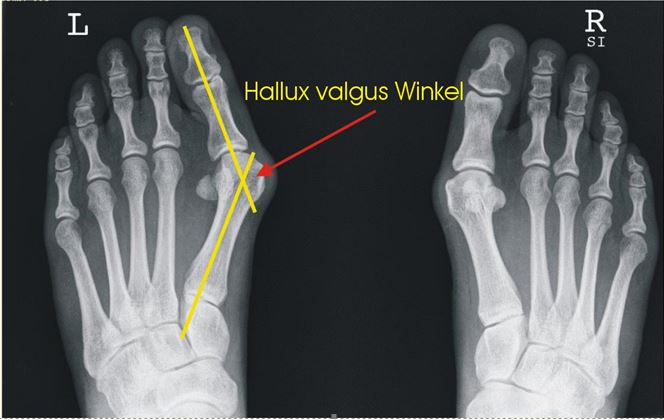

Hallux valgus - der Winkel wird vermessen

Der Musculus abductor hallucis zieht die Großzehe in die Valgusstellung (von der Körperachse weg) (siehe dazu Abb. 1). Eine Verkürzung des lateralen Seitenbandes und ein Überdehnen des medialen Seitenbandes fixieren die Fehlstellung. Eine Knorpelschädigung ist die Folge der inkongruenten Gelenksfläche. Das Köpfchen des Os metatarsale I weicht nach medial ab und verliert den plantaren (fußsohlenwärts) Kontakt zu den Sesambeinen. Dadurch wird das Sehnenungleichgewicht weiter verstärkt. Eine Kallusanlagerung medial am Köpfchen des Os metatarsale I mit Pseudoexostosenbildung verstärkt das prominente Großzehengrundgelenk noch weiter. Die Schuhdruckproblematik nimmt dadurch weiter zu.